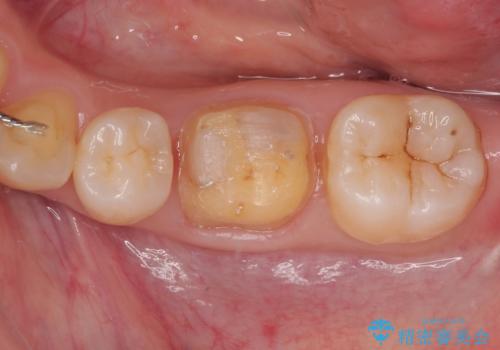

拡大鏡視野下で、金属の詰め物(メタルインレー)、虫歯の除去を行い、オールセラミッククラウンに適した形に整えました。

仮歯の状態で1週間ほど過ごしてもらい、しみる症状も改善されたので

歯と歯茎の間に圧排糸と言われる糸を入れてシリコーン印象材にて型どりをしました。